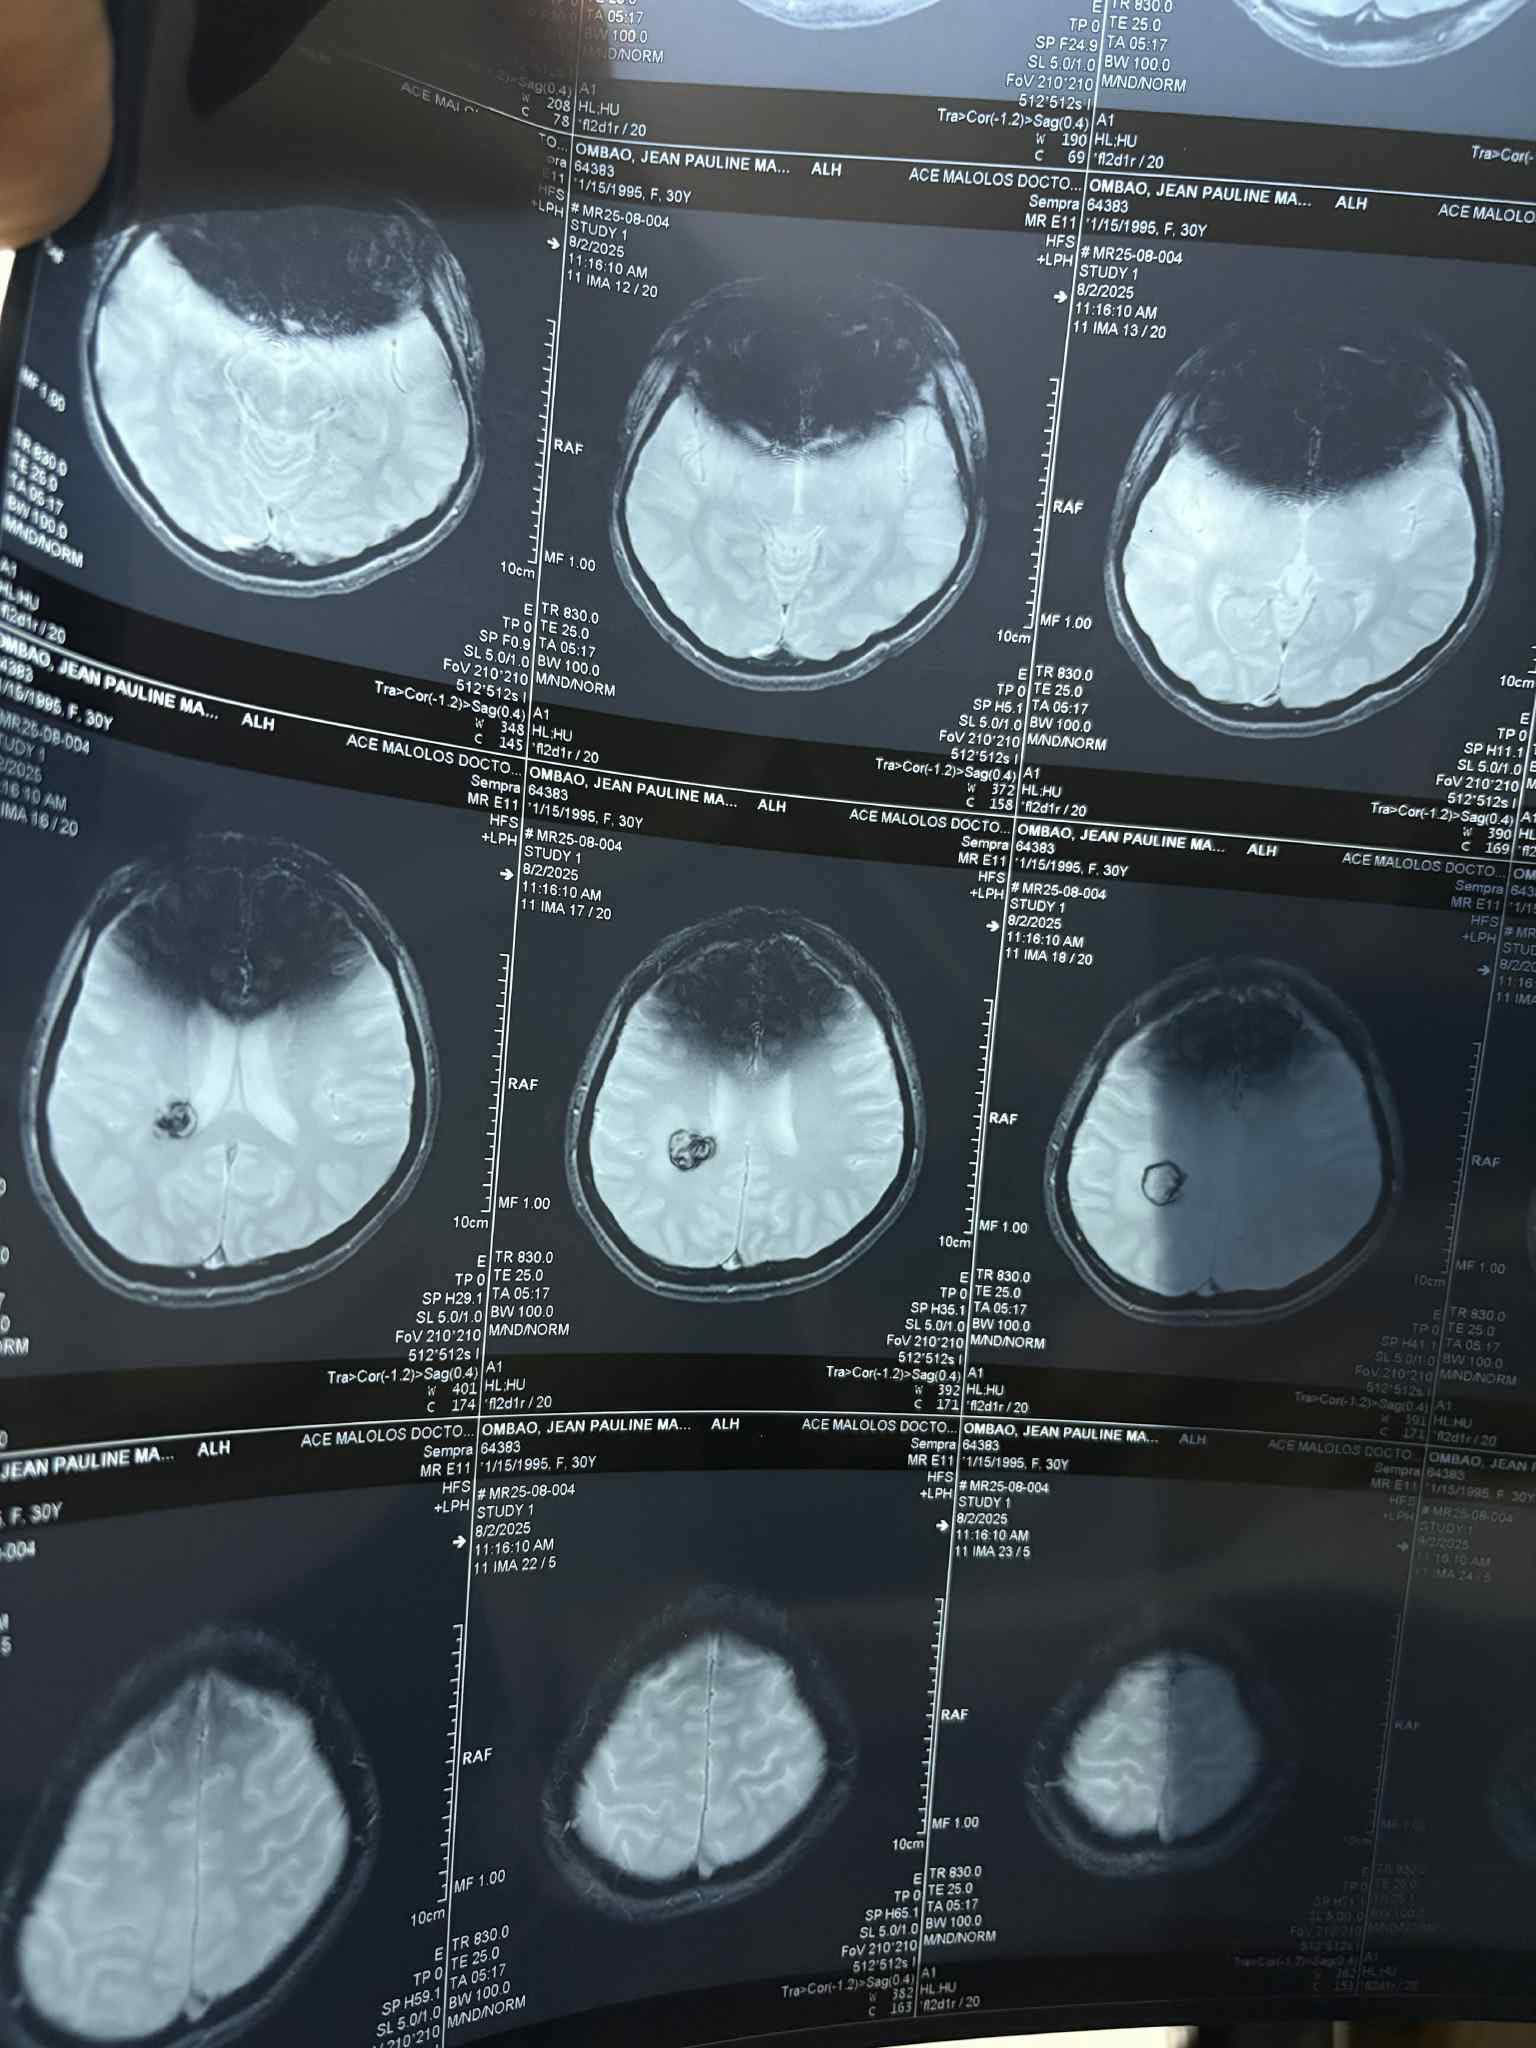

On March 20th of this year, Pau suffered a brain bleed that changed her life. After months of uncertainty, countless lab tests, CT scans, and an MRI, doctors discovered the true cause: a CAVERNOMA — a fragile cluster of blood vessels in her brain that can leak or bleed at any time.

Since Pau has already suffered one bleed, her doctors explained that the risk of another — potentially more severe, disabling, or even life-threatening — is extremely high. The only solution is urgent surgery to remove the cavernoma and prevent future bleeds.